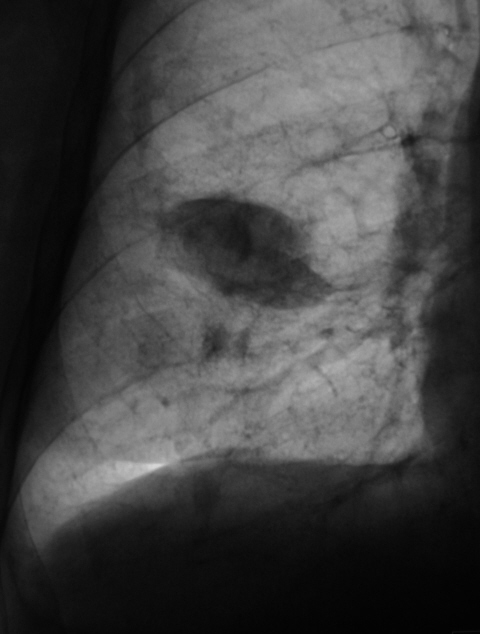

И фрагмент с увеличением. Что посоветуете tatyana ?

Конечно, я понимаю, что должна быть проведена д/д между "осумковнным выпотом" и "швартообразующим процессом". Что посоветуете?

Повезло с лаборантами!.. Поскольку, помимо междолевого ограниченого плеврита, мне мерещатся еще очаги в легком, посоветую КТ

Я пока, это никак не трактую. Случай сегодняшний, думаю. Может коллеги, чего подскажут. Вот и последний срез. Подумываю, что в наличии и "базальный" выпот.

Базвальный выпот, на мой взгляд, есть. А клиника какая7